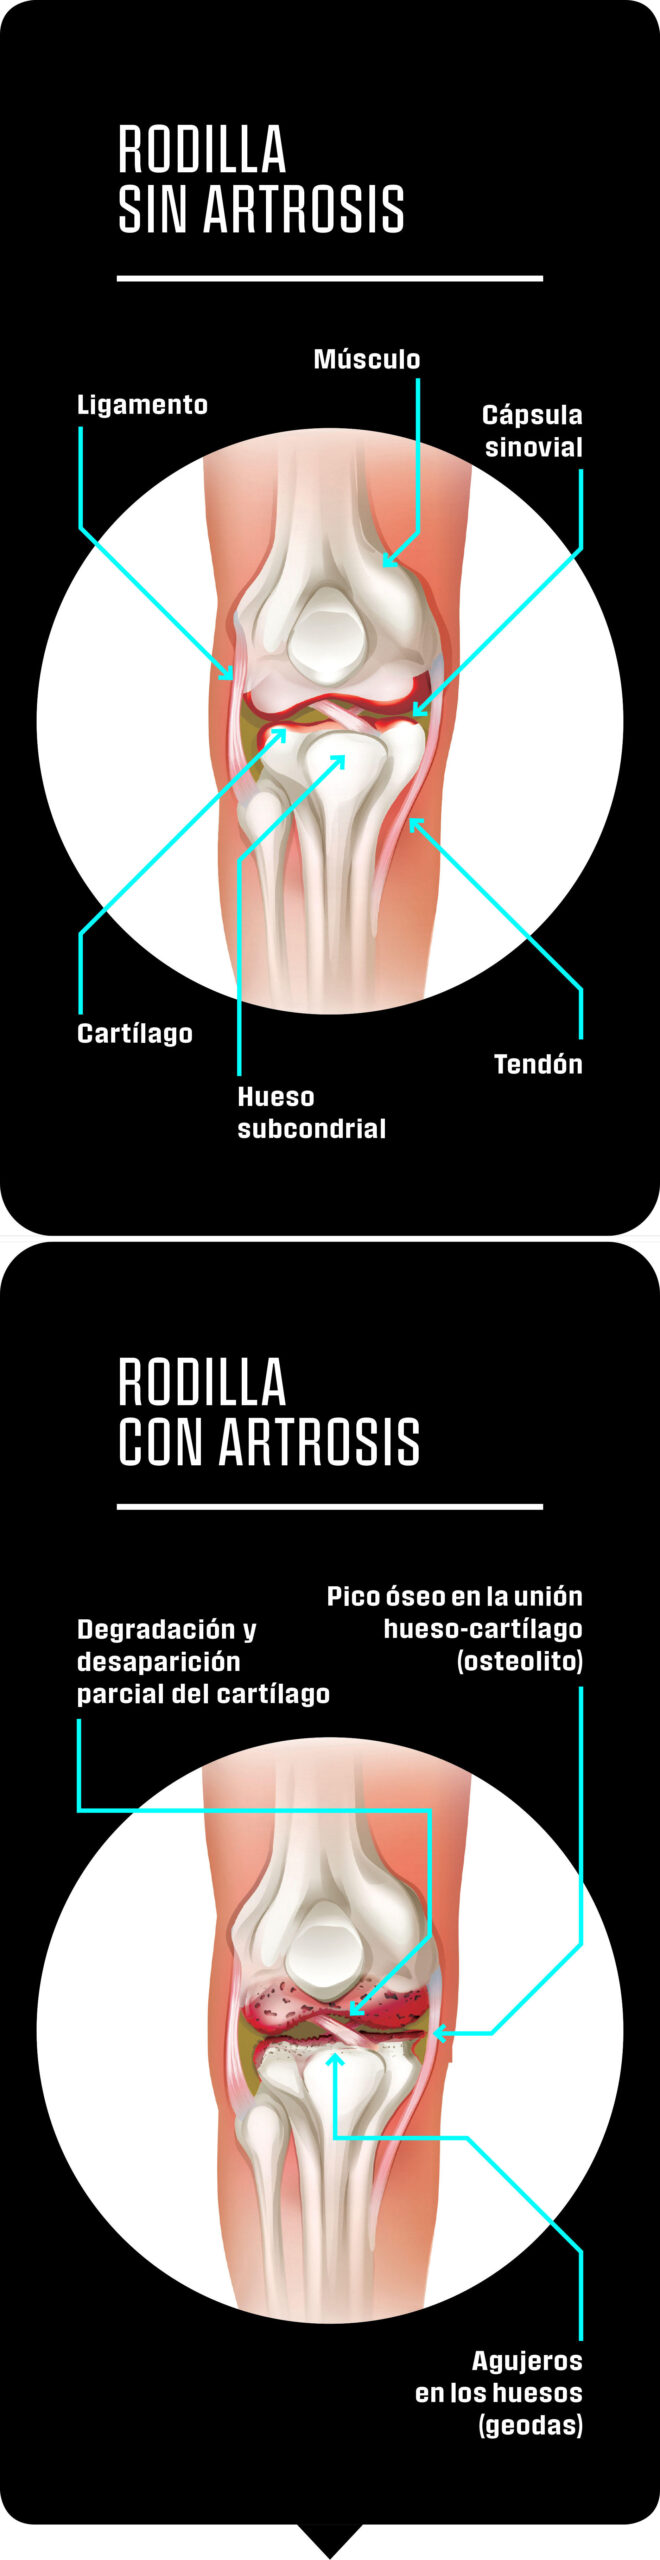

El cartílago permite que las piezas de la articulación tengan poco rozamiento entre sí. Cada vez más traumatólogos apuestan por el poder curativo del movimiento. Se cree que una actividad constante favorece la presencia de células madre en la zona, lo que podría regenerar el cartílago.

¿Qué es lo que me duele en realidad?

El cartílago contiene agua (un 70 por ciento), fibras de colágeno y otras proteínas (un 25 por ciento), así como células (cinco por ciento). Esta mezcla hace que las distintas superficies articulares presenten muy poco rozamiento entre sí. Esta eficacia se consigue mediante dos propiedades del cartílago: por una parte, presenta una superficie perfectamente lisa; por la otra, está recubierto por el llamado 'líquido sinovial'. Esta sustancia es de naturaleza viscosa y rellena los espacios entre los elementos que constituyen la articulación. No actúa solo como lubricante, sino que también aporta nutrientes al cartílago. Cuando falta esta capa de líquido milagroso, la articulación tira la toalla y empieza el dolor.

El cartílago es el eslabón débil de la articulación. Es posible ejercitar unos músculos vagos, es factible fortalecer unos huesos frágiles, pero el cartílago no cuenta con riego sanguíneo y no se puede fortalecer. Sí que contiene células. Y puede compensar pequeñas pérdidas y seguir cumpliendo con su misión durante mucho tiempo. No obstante, si se lo maltrata demasiado, acaba retrocediendo igual que ocurre con una encía inflamada. La persona afectada puede pasarse años sin percibir señales de este deterioro, pero un buen día desaparece la última capa de cartílago y los distintos elementos de la articulación empiezan a rozarse entre ellos. El dolor no te mata, desde luego, pero tampoco te deja vivir.

La artrosis transforma la articulación. Pueden aparecer excrecencias óseas, como protuberancias. Por otro lado, las células del sistema inmune atacan a los fragmentos sueltos de cartílago y producen una reacción inflamatoria de la articulación: la artritis.